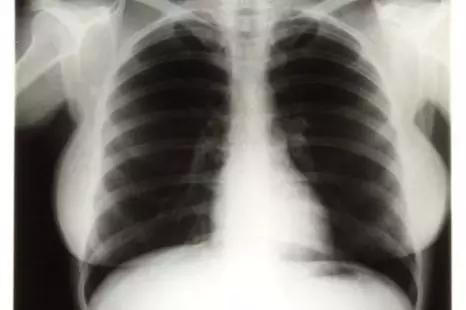

20世纪最著名女星,玛丽莲.梦露胸部X线,曾在拍卖上被拍出4.5万美元高价。